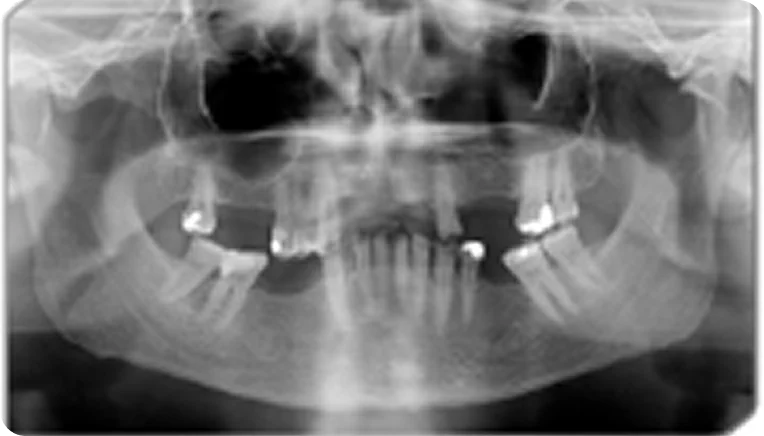

А теперь рассмотрим клинический случай нашего пациента.

Данные пациента [гипотетический пациент]:

Геннадий, 55 лет

• 1 класс по Кеннеди ВЧ, моляры и премоляры верхней челюсти утеряны в результате осложненного кариеса;

• в анамнезе декомпенсированный СД 2 типа;

• для пациента важна функциональность протеза, комфорт ношения и уверенность в фиксации;

• зубная формула представлена справа.

Пациенту рекомендовано изготовление съемного частичного зубного протеза